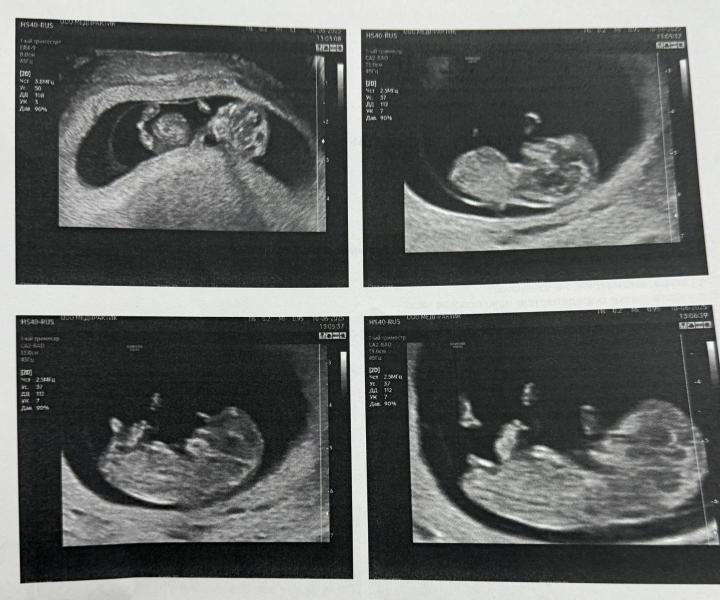

Кого видите? Говорят, если половой бугорок торчит кверху, то мальчик, параллельно позвоночнику - девочка. Узистка говорит пацан, по срокам ставит 11,2 дня (хотя по месячным 9,5) завтра иду кровь на определение пола сдавать, чтобы наверняка 🙈🤭

К стати, в роддоме срок ставили по самому первому УЗИ, а не по месячным.

По УЗИ уже больше, поэтому смотрят на него, врач сказала уже точно будет 👌